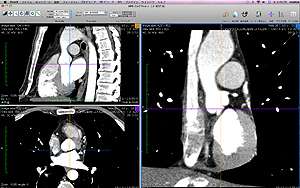

OsiriX(オザイリクス)という医用画像ビューワを日本で公式サポートしております。

OsiriX(オザイリクス)は、医用画像ビューワの表示とその画像からの分析す

るために開発された高性能なDICOMビューワです。また同時に DICOM通信

機能も備えた簡易的PACS としても利用可能な Mac OSX 専用アプリケー

ションです。無料でだれでもダウンロードできます。